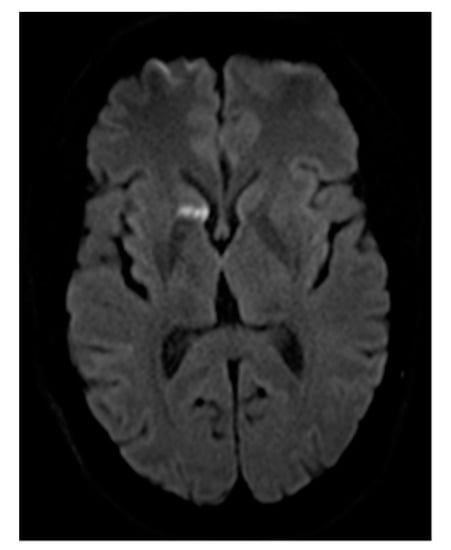

Figure 1. Cerebral DWI (b = 800) demonstrating subacute cerebral ischemia, in this case prior to embolization of multiple PAVMs. The newly developed lesion arose between screening for PAVM and the day of interventional therapy, but the patient did not exhibit any clinical signs or symptoms. This example highlights the importance of DWI for the detection of pre-existing cerebral ischemia, as well as peri-interventional cerebral insult.